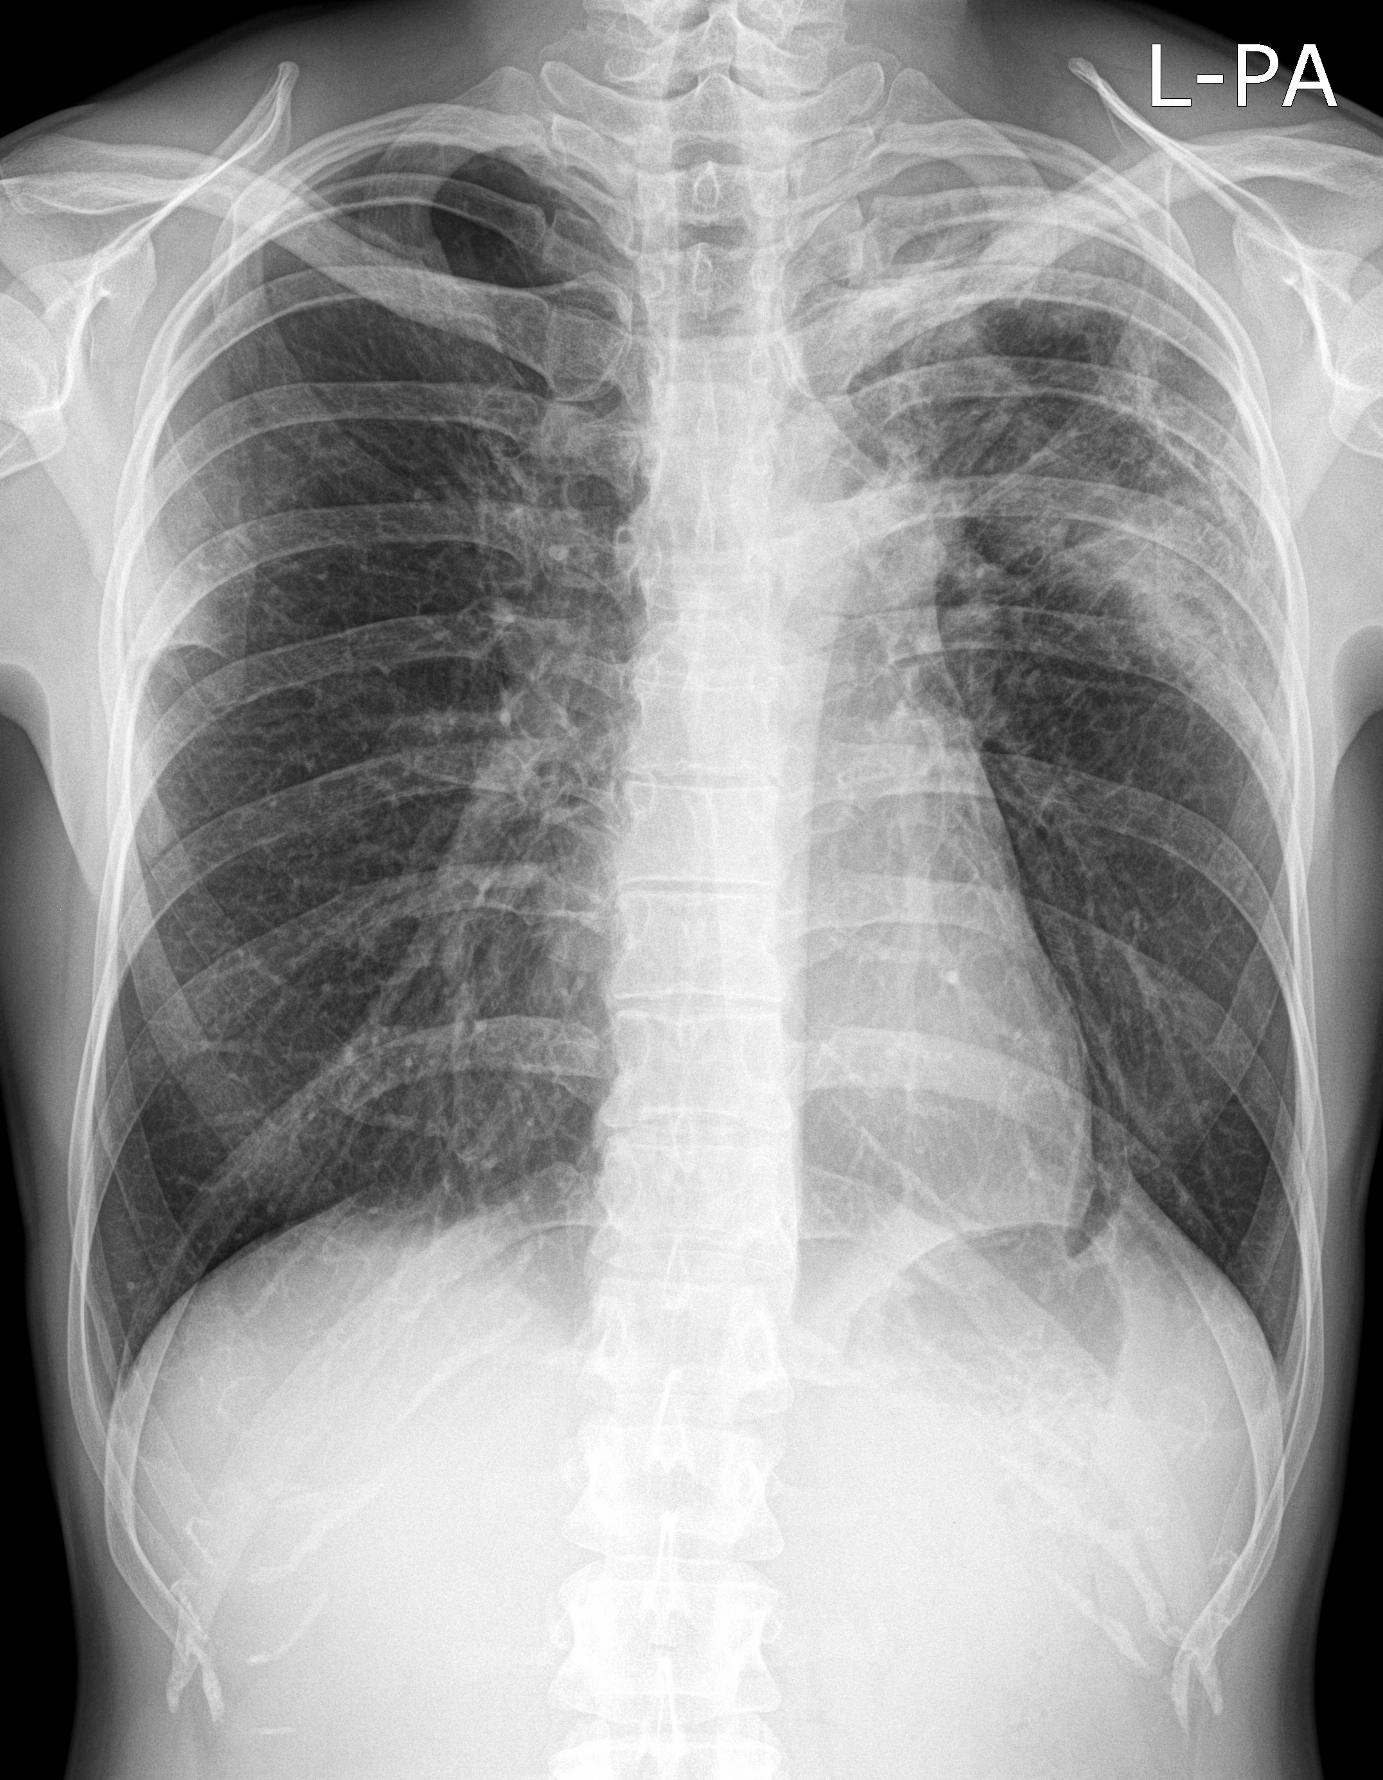

16. Right lobar pneumonia. a.) PA b.) lateral radiograph.

Mycoses